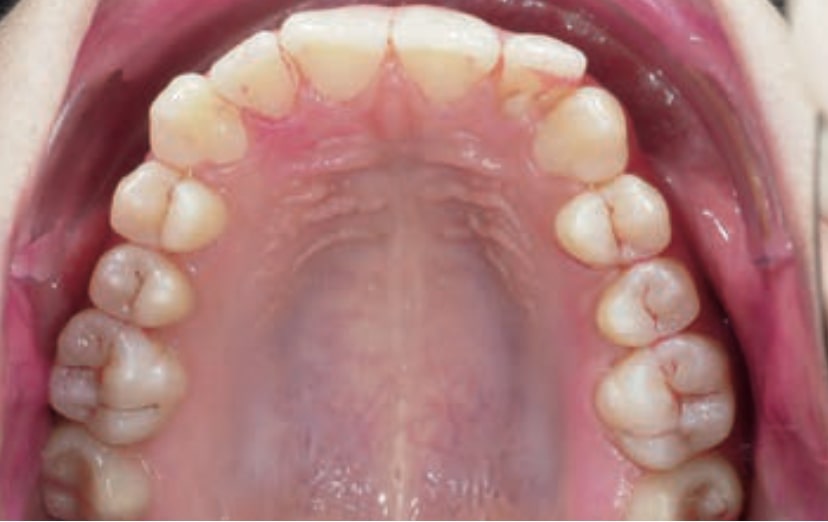

Chief complaint: The patient, a 19-year-old woman, was evaluated to undergo orthodontic treatment using the Angel Aligner Pro system. She presents with a skeletal Class III, mesofacial, with a dental Class III malocclusion and a 2 mm deviation of the lower midline to the left. Teeth 33 and 43 are out of the arch and cortical bone, with a crossbite issue on tooth 33. Fortunately, no functional issues affecting swallowing or breathing have been detected. The patient’s motivation for starting treatment was a general review of her dental and aesthetic health. The soft tissue analysis reveals mandibular protrusion that influences her facial profile. This diagnosis highlights the need for a comprehensive approach to address dental and skeletal misalignments, improving both the patient’s functionality and facial aesthetics.

• Dental Class III, 2 mm deviation of the lower midline to the left. 33 and 43 out of the arch and the cortical bone.

• Crossbite of 33.